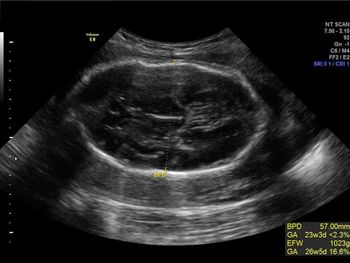

Challenge your diagnostic skills with this image of a fetal head.

Challenge your diagnostic skills: See anything out of the ordinary in this second trimester fetal heart study?